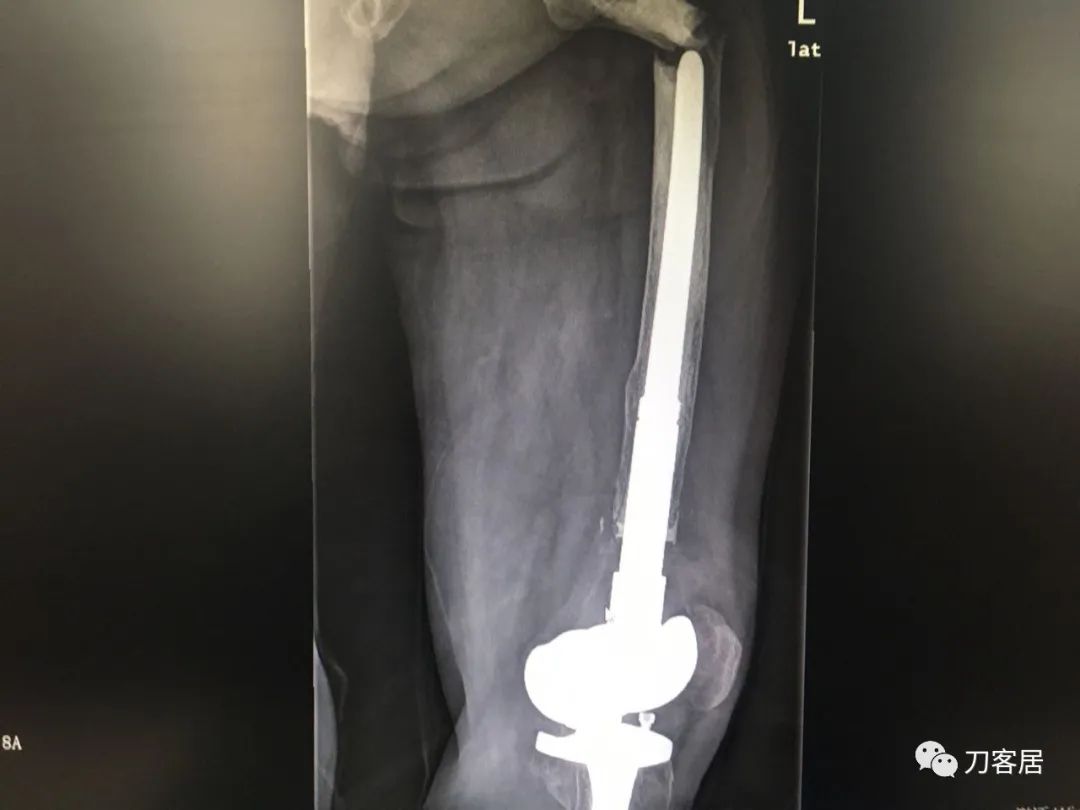

我不是中医黑2: 股骨髁上骨折,中药外敷治疗致股骨髁上陈旧骨折,县级中医医院手术,骨折病例用了骨肿瘤手术关节置换假体。

摘要: 这个病例第一次是摔伤致股骨髁上骨折,不知何种原因患者家属要求保守治疗,外包中药处理后骨折未愈合骨不连,后到一个县级中医院行了关节置换,选择的是肿瘤型假体。

现术后2年摔倒后致假体周围骨折。病人错误的选择,医生错误的治疗,最后导致不好的结局。

风吹麦浪10:25AM分享个病例,女性,67岁,外院手术后2年,现假体周围骨折。

风吹麦浪10:45AM这个病例第一次是摔伤致股骨髁上骨折,后不知何种原因家属要求保守治疗包中药处理后骨折未愈合骨不连,后到一个县级中医院行了关节置换,选择的是肿瘤型假体。

现术后2年摔倒后致假体周围骨折。

刘忠堂,长海关节10:52AM很简单的一例陈旧性骨折,断端硬化并没有太多影响,当时做一个坚强内固定,就可以解决问题,却选择了这样一个方式,2年后出现假体周围骨折,目前也只能做内固定

刘忠堂,长海关节10:54AM锁定钢板,骨折远端半皮质螺钉,周围异体皮质骨板钛缆固定

何川2:58PM我是坚决反对这种病例一期做置换。如果,实在要做假体,要做好精细严密的术前计划,这是骨折病例,不是肿瘤,那些碎掉的骨块完全可以利用起来,延长杆就不需要用很长了。

从X片看没有涉及副韧带止点,可以保留重要骨块,加内固定钢板辅助,非限制性假体即可,实际用了铰链、这么长的杆,全髓腔骨水泥,基本打定主意一锤子买卖,把自己后路全断了。